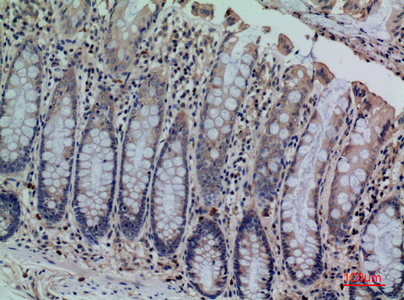

- Scientific DescriptionRabbit polyclonal antibody to CDCP1.